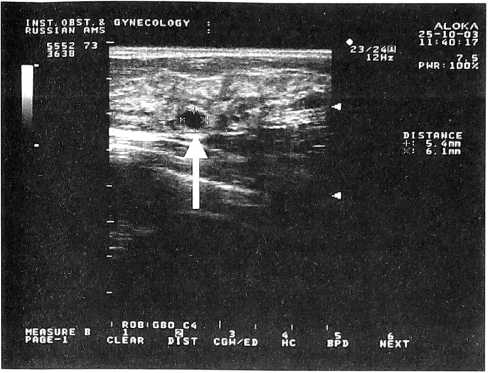

Рис. 2.

Эхограмма молочной железы при наличии фиброзного варианта мастопатии. Эхогенность железистой ткани усилена (границы железистой ткани отмечены стрелками)

Увеличение толщины паренхимы, средняя эхогенность железистой ткани, отсутствие или слабая выраженность явлений жировой инволюции, расширение протоков характерны для железистого варианта мастопатии (рис. 1); значительное повышение эхогенности железистой ткани с увеличением толщины паренхимы — для фиброзного (рис. 2); наличие множественных кист различного диаметра — для кистозного (рис. 3). Сочетание различных симптомов мастопатии характерно для ее смешанного варианта.